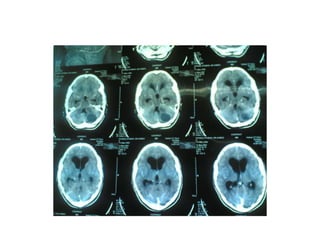

Investigation U ltrasonography to visualize the ventricular system(when the anterior fontanelle is patent). Also for antenatal diagnosis CT and /or MRI of the head; it is important to exclude any abnormal masses and to study the size and the shape of the ventricles, and some time needs contrast study.  LP in cases of communicating hydrocephalus for both diagnostic and therapeutic…..( NPH)

Investigation U ltrasonographyto visualize the ventricular system(when the anterior fontanelle is patent). Also for antenatal diagnosis CT and /or MRI of the head; it is important to exclude any abnormal masses and to study the size and the shape of the ventricles, and some time needs contrast study. LP in cases of communicating hydrocephalus for both diagnostic and therapeutic…..( NPH)